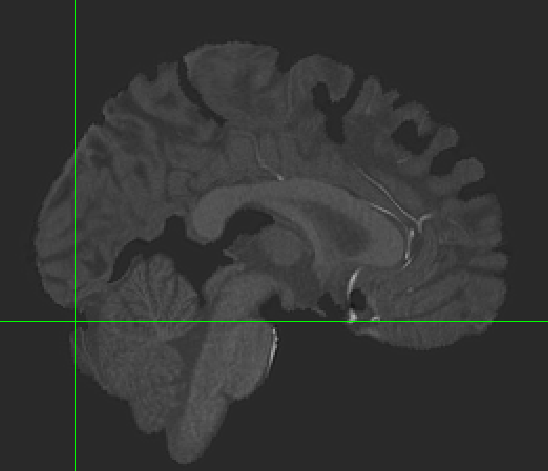

Hi all, I’m hoping to get some suggestions for how to handle alignment in my dataset. I have 3T BOLD images for a set of participants whose structural scans were collected at 7T. When I run fmriprep, the cortex seems to align well between BOLD and T1w images, but everything subcortical looks shifted. The brainstem looks misaligned, and the cerebellum as well. I’ve tried several things and can’t seem to resolve the problem. I’ll post the general code that I’ve used below with a list of different commands I’ve tried.